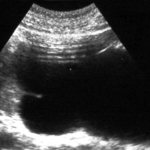

Диагностируют мочекаменную болезнь почек с помощью УЗИ, бесконтрастной компьютерной томографии, экскреторной урографии (рентгенологический метод исследования мочевых путей). Также пациенту рекомендуют сдать анализ мочи на количество эритроцитов, лейкоцитов, тест на бактериурию – количество и вид бактерий, посев мочи.